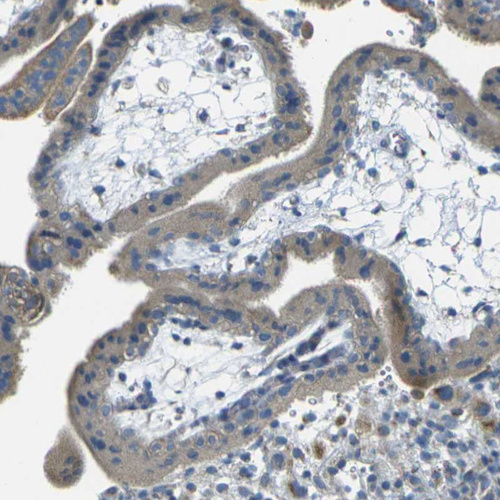

Immunohistochemical staining of human kidney shows weak to moderate cytoplasmic positivity in cells in tubules.